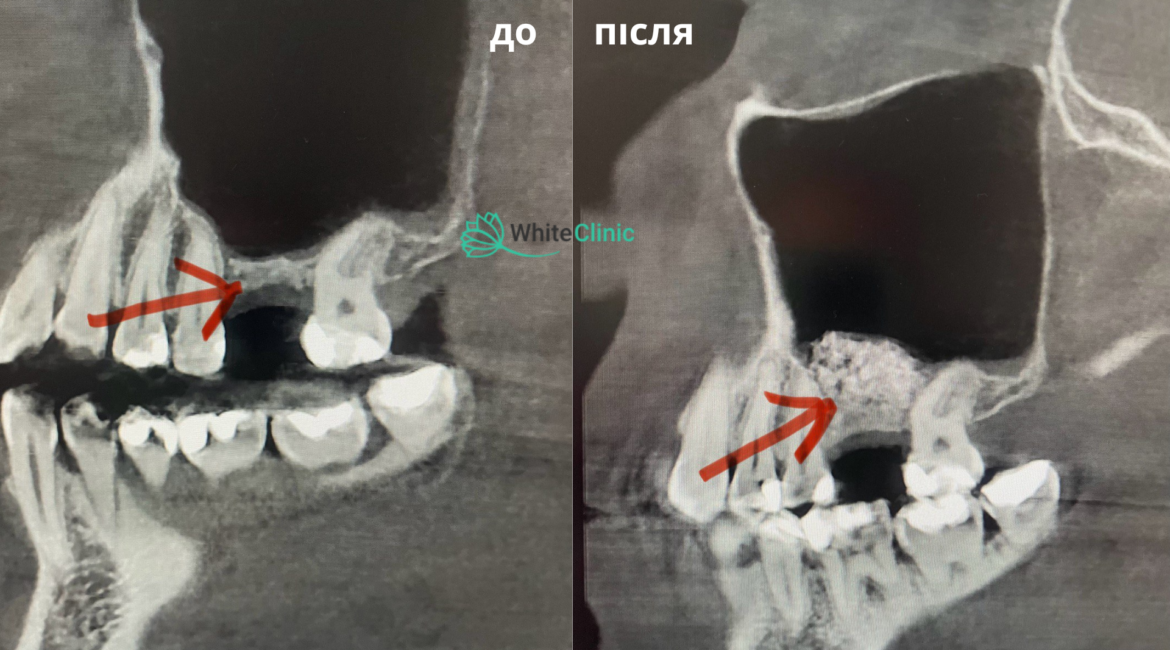

Щоб зберегти молодість і чарівність надовго, знадобиться візит до стоматолога. Для пацієнтів центру White Clinic доступна кісткова пластика – сучасна хірургічна процедура, яка передбачає нарощування та модифікацію форми кісткової тканини верхньої чи нижньої щелепи.

- Синус-ліфтинг – методика, ефективна для відновлення тканин верхньої щелепи. Полягає в заповненні гайморової пазухи синтетичним матеріалом.